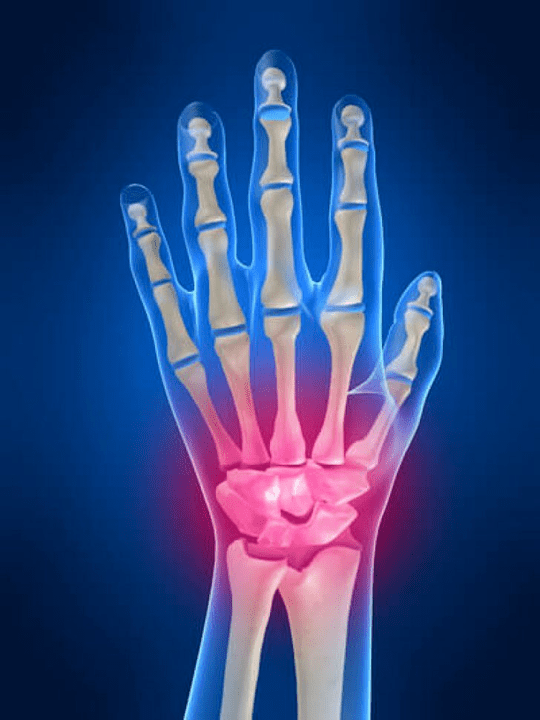

Dor nas articulacións Os dedos son un signo indispensable dunha patoloxía común na que os compoñentes estruturais destes compostos están danados. En primeiro lugar, a dor na zona destas articulacións pode asociarse a varias enfermidades autoinmunes (Brillo vermello sistémico, artrite reumatoide, artrite de psoríase, etc.) en que os factores inmunitarios danen o seu propio tecido articular.

A seguinte razón principal que poida iniciar dor Pode haber feridas na puta dos dedos (Contusións, transferencias, ósos rotos, ligamentos). A dor nestas articulacións tamén se pode provocar por cambios dexenerativos nos seus tecidos articulares. Isto pódese observar a miúdo na artrosis.

Que estruturas poden acenderse nas articulacións das mans?

A inflamación é un proceso patolóxico típico característico destes tecidos e órganos que foron danados por algún motivo. Hai que lembrar que na maioría dos casos todas as enfermidades (Por exemplo gota, artrite reumatoide, etc.) ou trauma que danan as conexións das mans a un ou a outro grao non só afecta á articulación, senón tamén ao periert (Nervios, músculos, tendóns, graxa subcutánea, pel) Estruturas.

As seguintes estruturas articulares poden acenderse nas articulacións das mans:

- cartilaxe común;

- Espremer o tecido óseo;

- Cápsula conxunta;

- Ligamentos comúns.